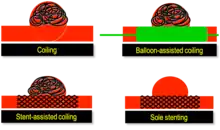

New techniques: Sole stenting and flow diversion stents

From the early 2000s, intracranial stents were used to prevent the coils inside the aneurysmal sac from protruding into the parent artery.[11][12] Flow diversion devices were later developed, with the function of reconstructing the vessel's normal anatomy without directly closing the aneurysm neck and therefore preserving side branches and preventing ischemia.[13] The sole stenting[14] procedure involves the insertion of a stent only (without any coils) into the vessel that has an aneurysm.[15]